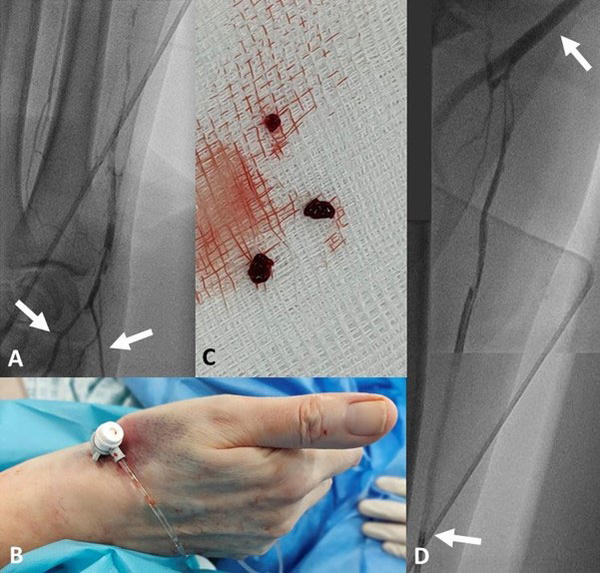

Figure 1

1A – Superficial palmar arch branch (left arrow) and Microcatheter (right arrow).

1B – dRA approach with a 5Fr “femoral” sheath.

1C – Aspirated thrombi.

1D – Recanalized RA with residual thrombi, tip of guide (lower arrow) and brachial artery (upper arrow).

Despite this, the artery was accessed via the distal RA (dRA) using the 2-step cannulation technique we previously described1, initially with a pedal-access microcatheter (Cook Medical, Bloomington, IN, USA). Radial arteriogram (Figure 1A, Video 1) confirmed a thrombosed RA.

Next, a 0.035” J-tipped wire, which is more supportive, was used to swap in a 5Fr “femoral” sheath (Figure 1B), and a 4Fr JR4 catheter was advanced to the RA ostium, aspirated and flushed, and heparin was given to avoid thromboembolization.

The guide was then withdrawn from the RA and aspiration thrombectomy performed (Figure 1C), with improved flow down the RA (Figure 1D, Video 2).